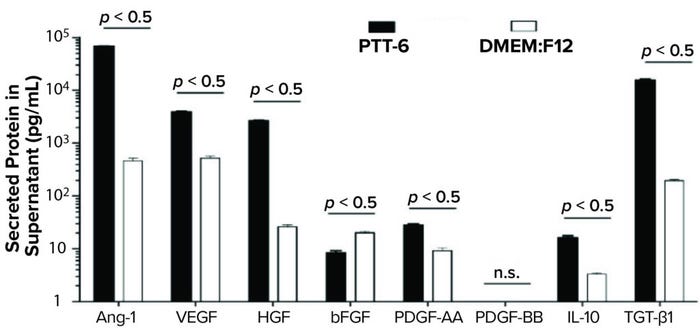

To study potency and therapeutic potential of our MSCs following multiple passages, we used a cytokine secretion assay. Results showed significantly higher secretion levels (p < 0.05) of IL-10, VEGF, PDGF-AA, Ang-1, HGF, and TGF-β1 in PTT-6–cultured MSCs than in DMEM:F12–cultured cells. By contrast, DMEM:F12–cultured MSCs showed significantly higher secretion levels (p < 0.0001) for bFGF. No PDGF-BB secretion was detected in any experimental conditions (Figure 7).

Figure 7: Secreted proteins from cells cultured as indicated and quantified by human magnetic Luminex assay. PTT-6 MSCs showed significantly higher levels of IL-10 (16.1 ± 1.6 pg/mL), VEGF (3,898 ± 171.9 pg/mL), PDGF-AA (28.2 ± 1.4 pg/mL), Ang-1 (67,653 ± 1,261.2 pg/mL), HGF (2647 ± 101.7 pg/mL), and TGF-β1 (15,590.3 ± 486.3 pg/mL) than those of MSCs cultured in DMEM:F12, which were 3.3 ± 0.2 pg/mL for IL-10, 521 ± 47.7 pg/mL for VEGF, 20.2 ± 1.3 pg/mL for bFGF, 9.2 ± 1.2 pg/mL for PDGF-AA, 465 ± 57.6 pg/mL for Ang-1, 26 ± 2.4 pg/mL for HGF, and 195.5 ± 8.4 pg/mL for TGF-β1. The latter group secreted significantly higher levels of bFGF (20.2 ± 1.3 pg/mL) than those cultured in PTT-6 (8.4 ± 0.8 pg/mL). No PDGF-BB secretion was detected in either group, and a total of three biological replicates were analyzed for each set of conditions.

Use of MSCs for treating wounds with chronic inflammation has been studied clinically (28, 29). Critical proangiogenic factors (e.g., Ang-1, VEGF, HGF, bFGF, PDGF-AA, and PDGF-BB) and antiinflammatory cytokines (e.g., IL-10 and TGF-β1) have been identified as playing important roles in the acute inflammatory, proliferative, and remodeling phases of wound healing (30). Moreover, the ability of MSCs to secrete high levels of proangiogenic and antiinflammatory cytokines has been shown to enhance wound healing (31). Here, we have observed significantly higher secretion levels of Ang-1, VEGF, HGF, PDGF-AA, IL-10, and TGF-β1 from PTT-6–cultured MSCs than from DMEM:F12–cultured MSCs, which had significantly higher secretion levels of bFGF. Negligible secretion levels of PDGF-BB were quantified in all experimental conditions.

The lower secretion levels of bFGF and PDGF-BB in our results are in agreement with a previous study suggesting that neither of those angiogenic factor plays a key role in angiogenesis during wound healing (32). We included our list of proangiogenic factors as part of CGMP manufacturing potency control, which has been vetted and approved by the US FDA for chemistry, manufacturing, and controls (CMC).